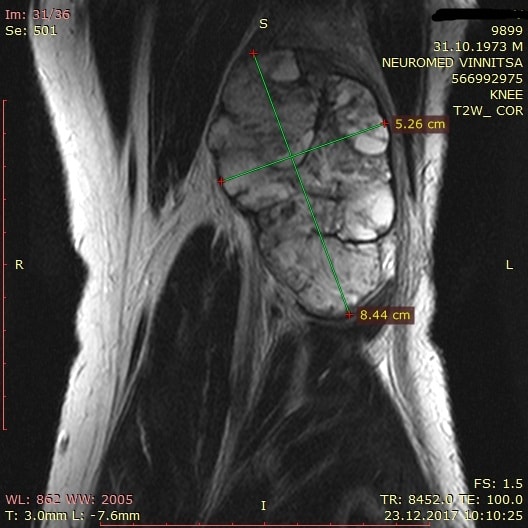

Re: Новообразование на задней поверхности коленного сустава

еще снимки